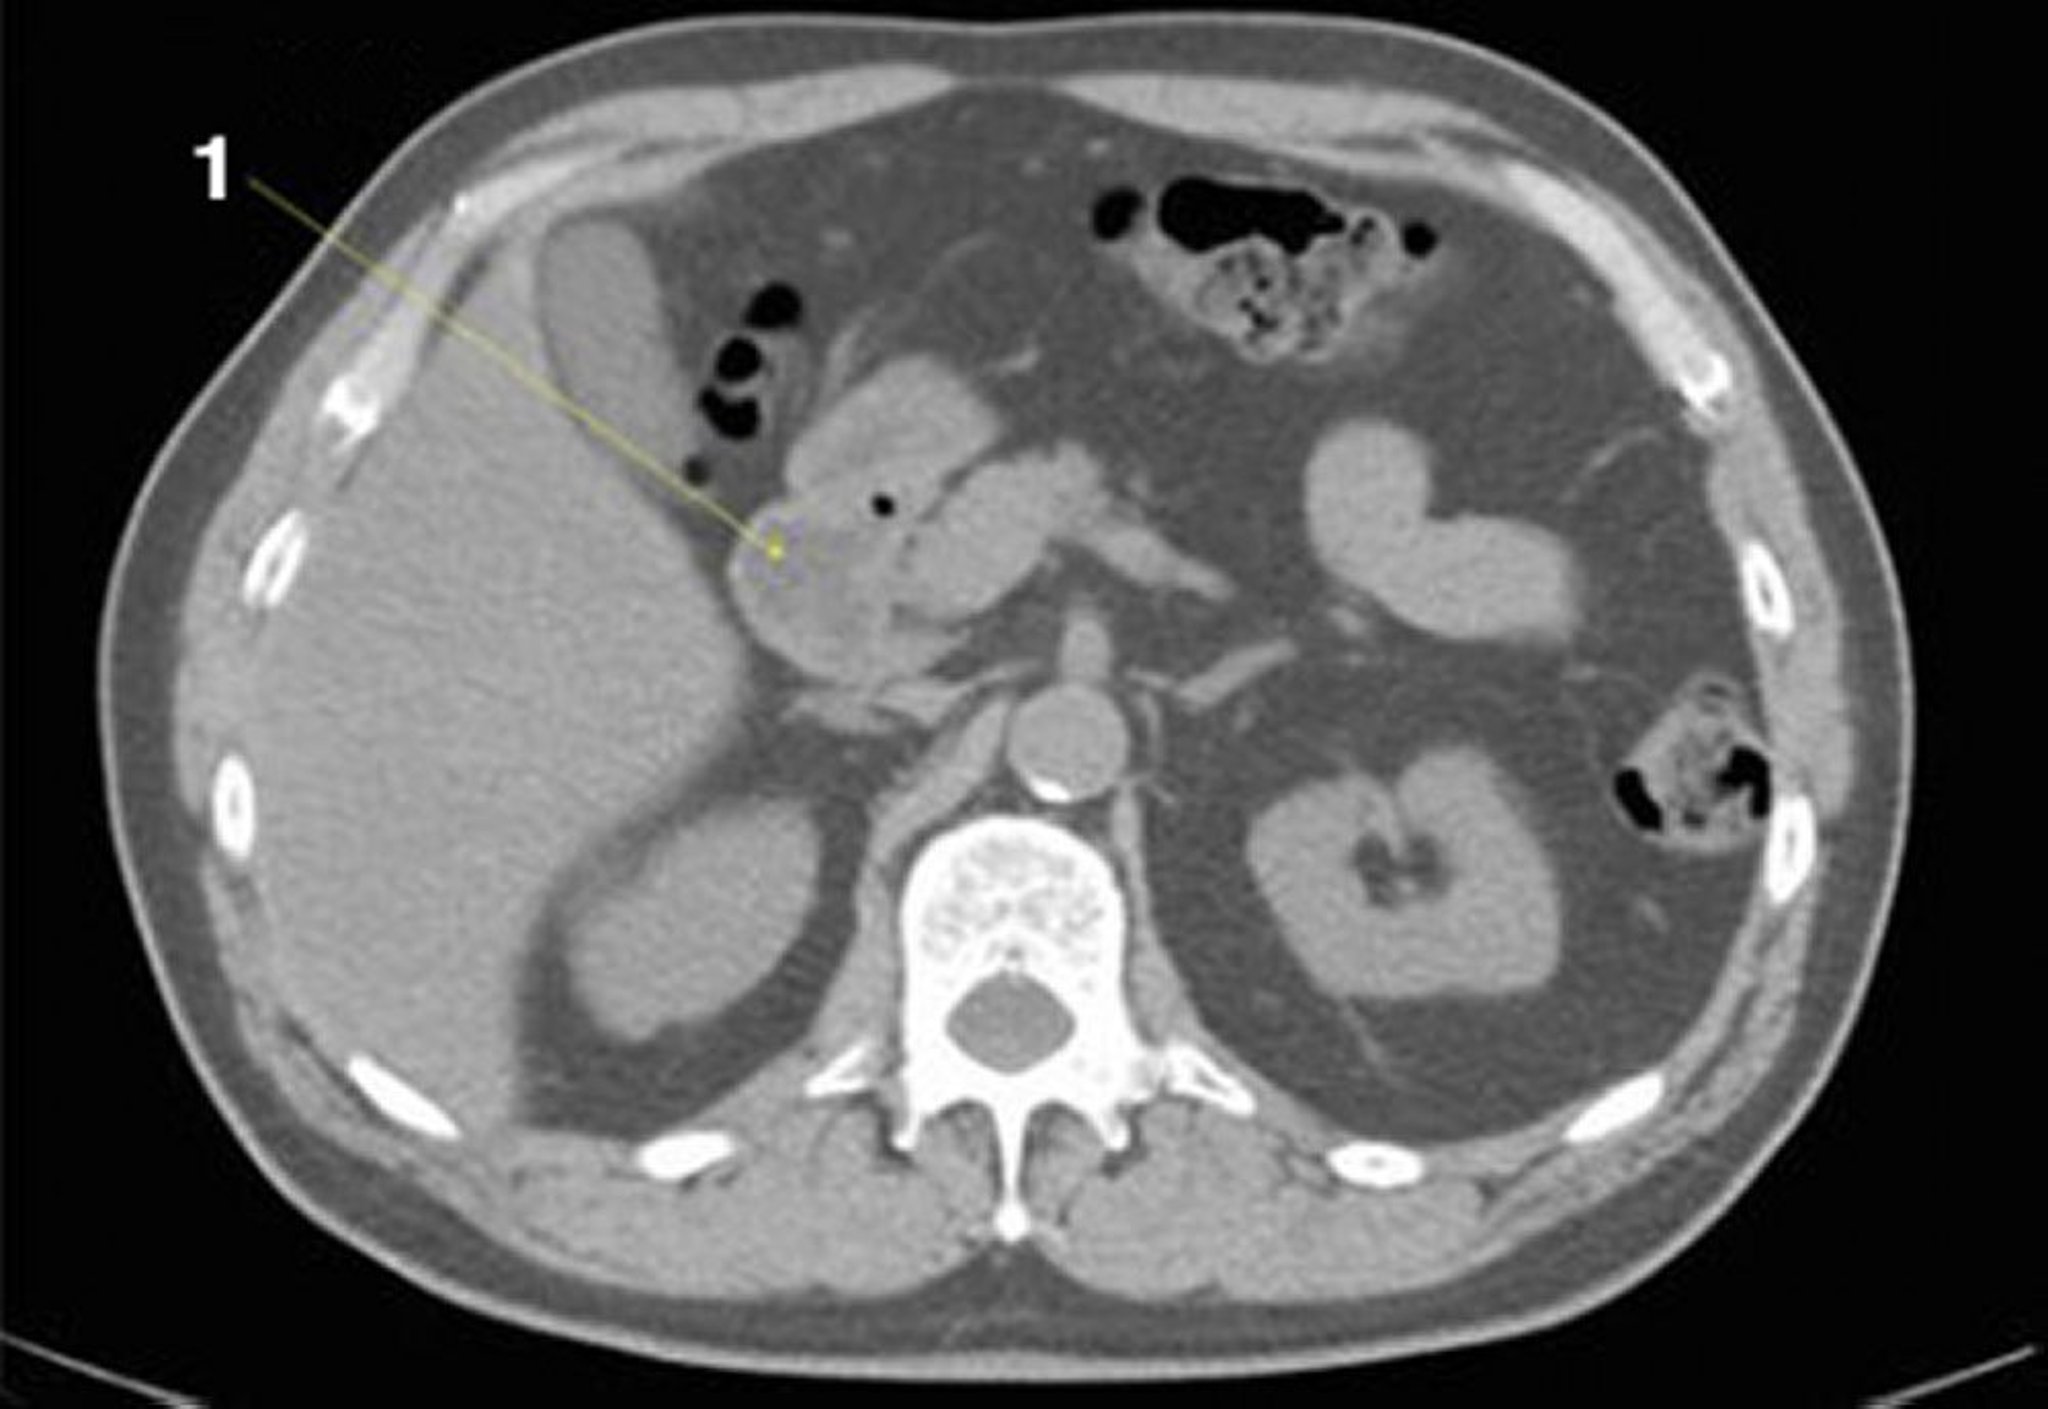

CT-Scan von Abdomen und Becken mit normaler Anatomie ohne Kontrastmittel (Folie 11)

1 = Duodenum.